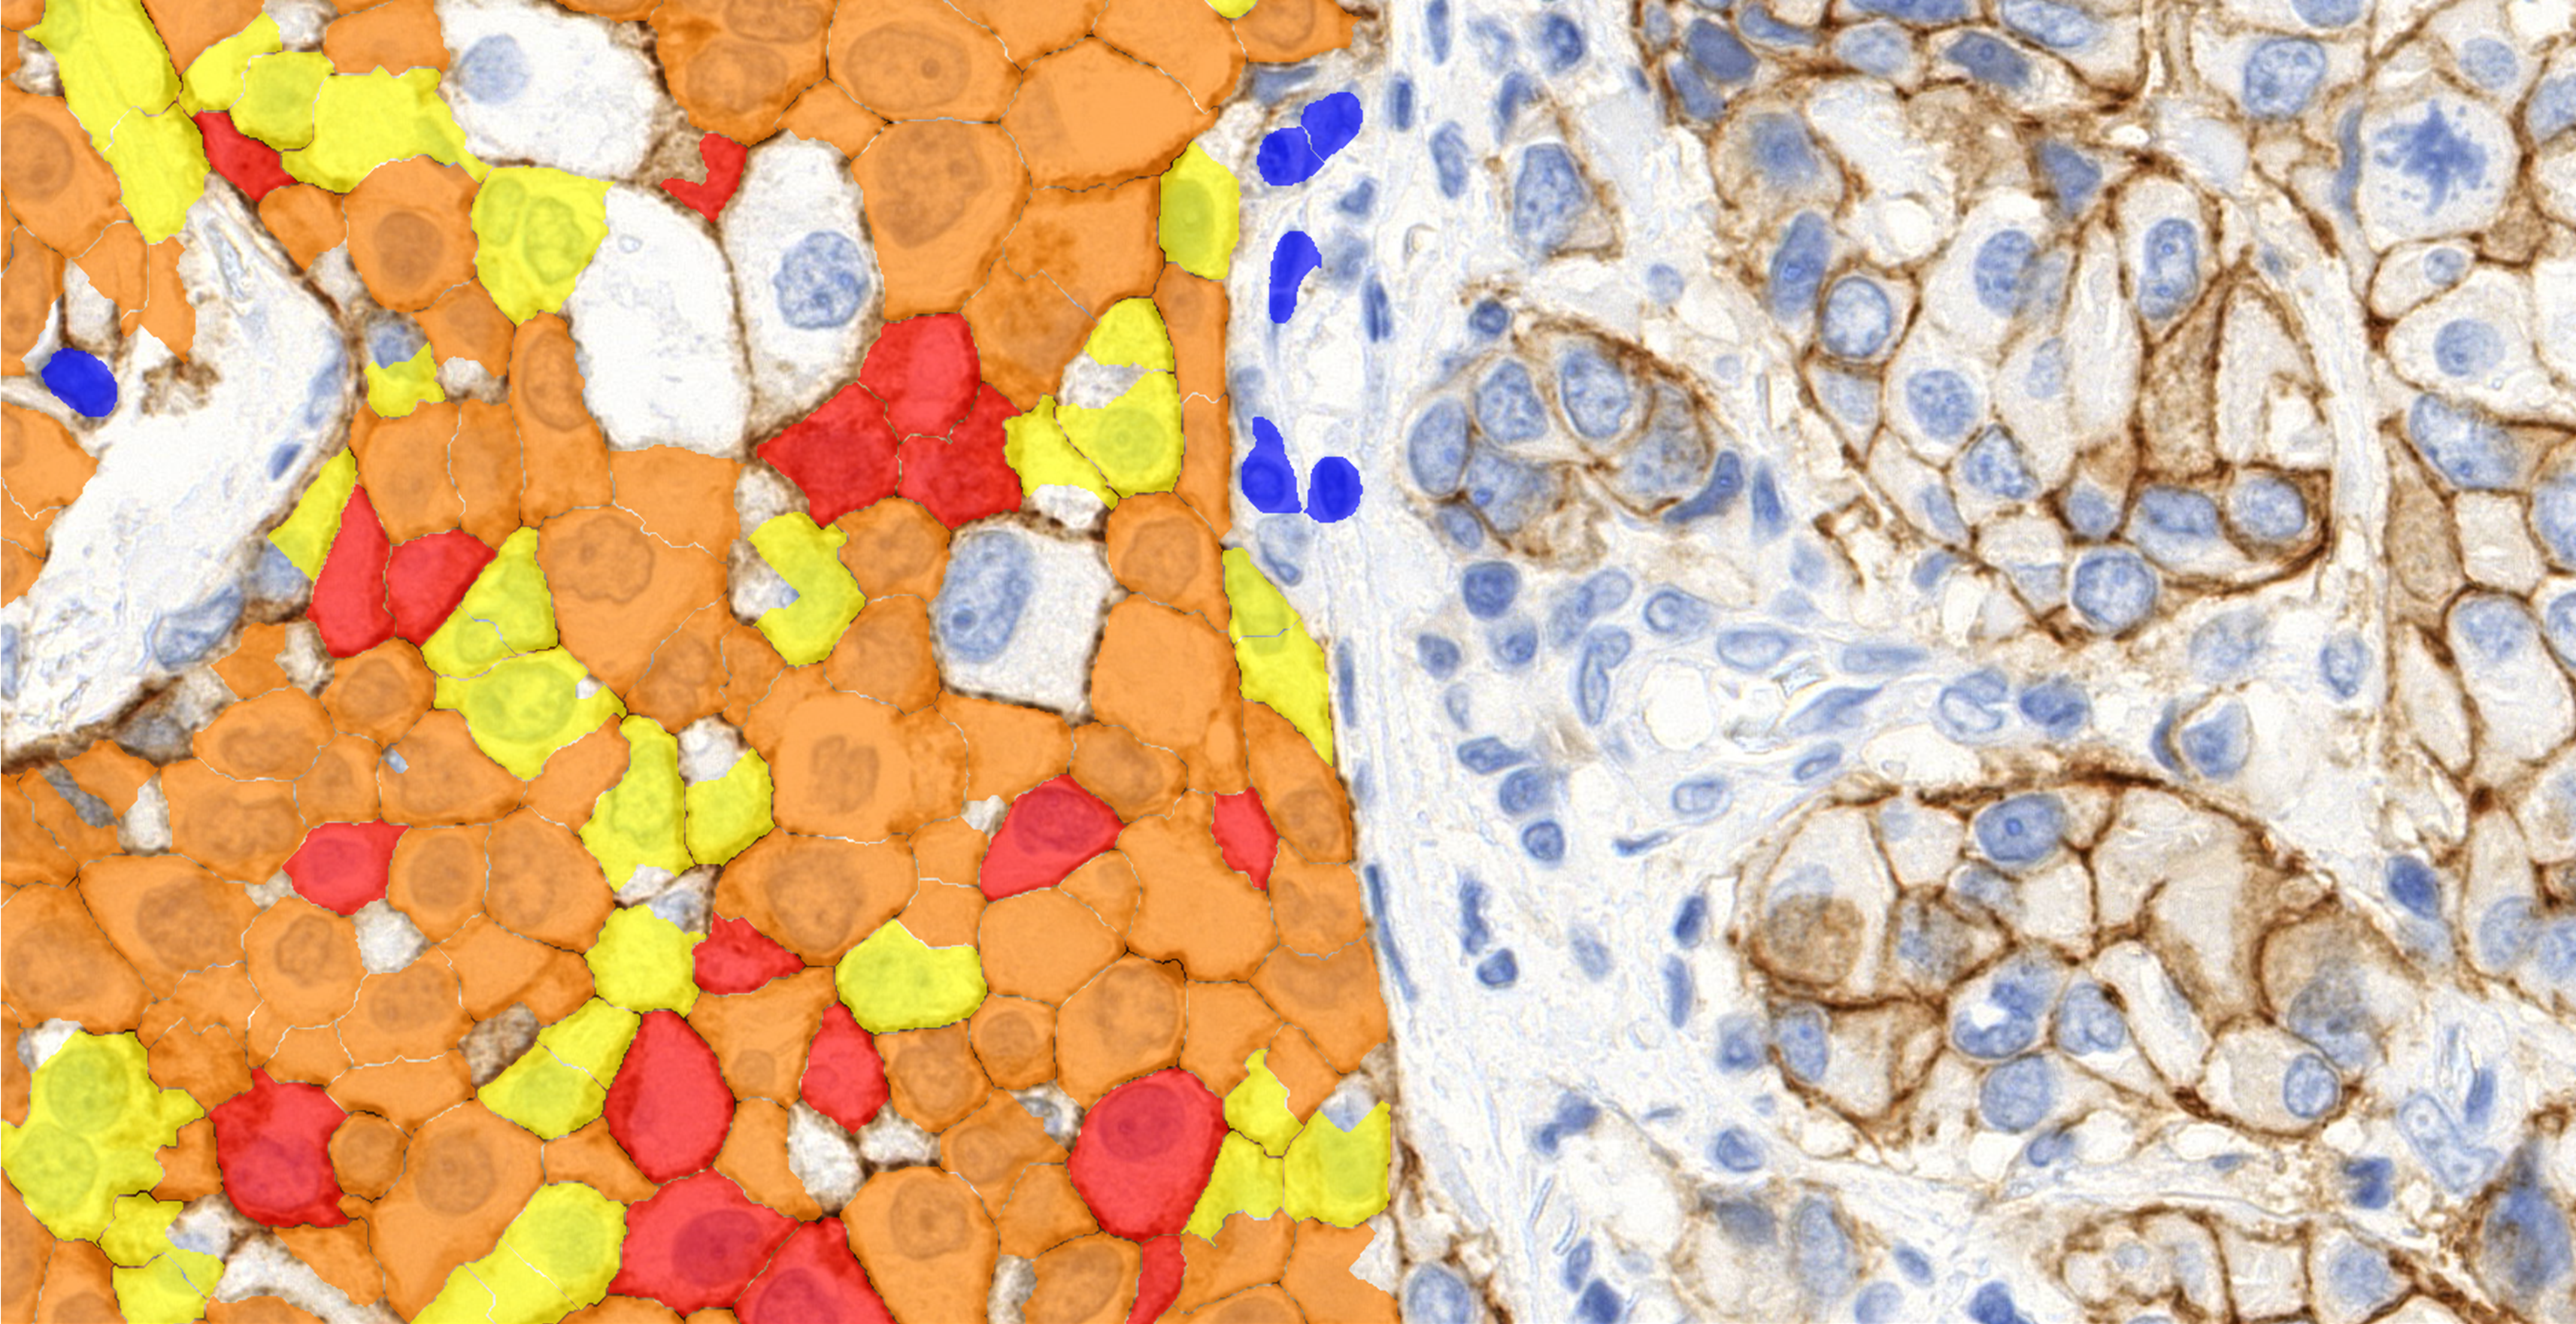

A special IHC color calibration option is integrated into these quantification modules, facilitating software integration to the local laboratory. By applying this function the software can be calibrated to the sample quality (local laboratory stain protocol, or different stainer), resulting in an adequate measurement.

MembraneQuant is a cell membrane detection software application that can be used for the quantification of IHC stained histological samples. This module measures cell morphology and stain density, reports intensity-based core ranges, overall scores and positivity percentages (including H-Score), distinguishing the continuous membrane stain from the moderate stain.